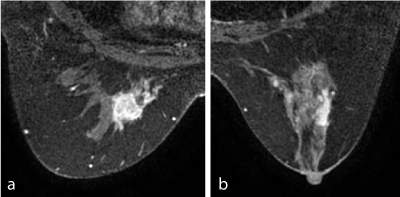

Figure 1. Contrast-enhanced MRI findings of the first and second lesions.

Case 1

a:      The contrast-enhanced image shows a 23-mm mass suggestive of IDCa.

b:      The contrast-enhanced scan displays an 8-mm nodule suggestive of IDCa. Pathology: 8-mm IDCa.

Case 2

a:      Segmental enhancement suggestive of IDCa.

b:      16-mm mass with irregular margin suggestive of IDC. Pathology: 20-mm IDCa.